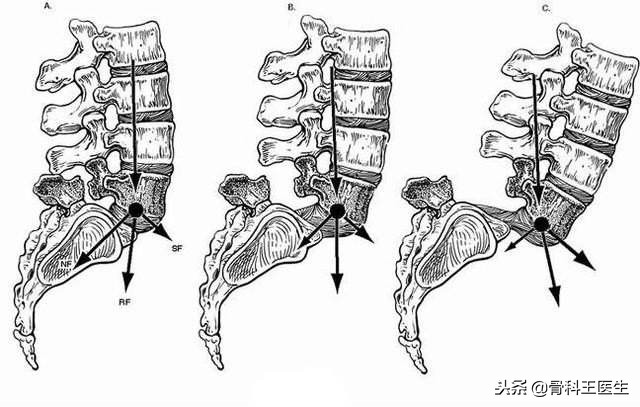

腰椎滑脱说白了就是相邻腰椎之间出现了位移,可以很轻微,也可以很严重。下图就是由轻到重:

腰椎滑脱